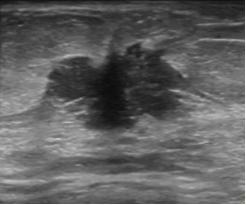

4.乳腺结节的内部回声。

分为:无回声、低回声、等回声、高回声和混合性回声。不均匀低回声的结节多为恶性,混合性回声多为囊实性结节,其恶性的可能>10%。

结节内回声不均,术后病理为恶性